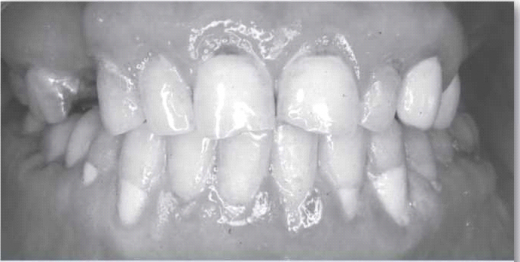

כאשר יש ירידה בהפרשת הרוק, פעולות שגרתיות כגון אכילה, בליעה או דיבור הופכות להיות קשות יותר ויותר. מצב של מחסור ברוק גורם גם לפגיעה בחוש הטעם, להופעה של פצעים בפה ולתחושה של צריבה בפה (תחושה של צריבה ו"שריפה" אופיינית לזיהום פטרייתי). ניתן לראות עששת אופיינית בשורשי השיניים וקושי בהרכבה ובהצמדה של תותבות.[2], [3], [4] במצב מתקדם ייאלצו הסובלים ממחסור ברוק לשאת עמם בכל עת בקבוק מים כדי ל"הרטיב" את הפה ולאפשר אכילה ובליעה. בשל היובש בפה, קשה מאוד להירדם ולישון. קושי זה יכול לגרום להסתגרות ולבידוד חברתי, ואף להוביל לדיכאון.

כדי להגן על השיניים מפני נזק נוסף, חשוב לשמור על היגיינת (Hygiene) פה טובה ולהשתמש במשחת שיניים המכילה פלואוריד (Fluoride) על בסיס יומי.[3] נוסף על כך, מומלץ להשתמש במוצרים כמו אלמקס ג'ל. בתכשיר זה ריכוז גבוה של פלואוריד, ולכן מומלץ להשתמש בו רק יום בשבוע במקום משחת השיניים הרגילה. כמו כן, חשוב להימנע משתייה או מאכילה של דברי מתיקה ולהקפיד על מעקב ועל ביקורת צמודה של רופא השיניים.